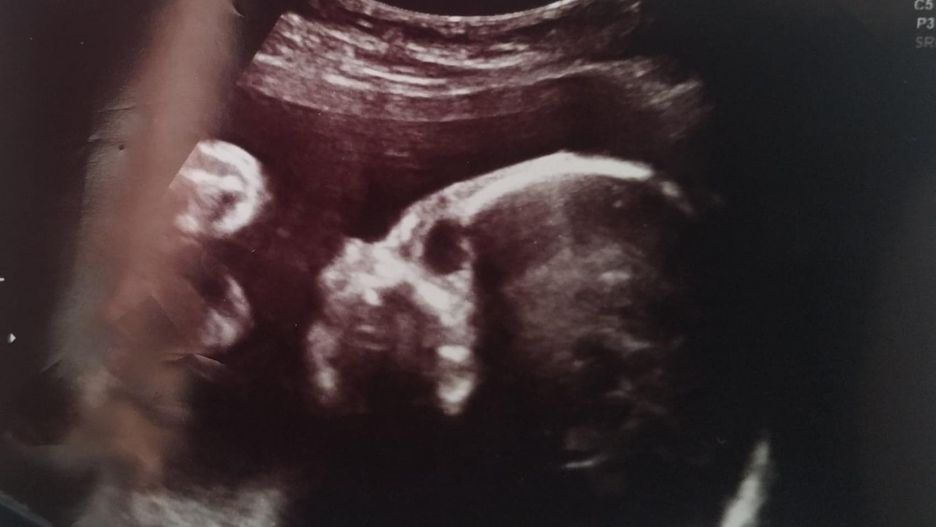

Płód z zespołem EdwardsaPłód z zespołem Edwardsa

Źródło zdjęć: © mat.pryw

W trakcie badania USG lekarz stwierdził u płodu szereg wad.

Dariusz Piontkowski o planach MEN dotyczących pomocy psychicznej dla dzieci

U płodu stwierdzono szereg wad

U płodu stwierdzono szereg wad © mat. prywatne